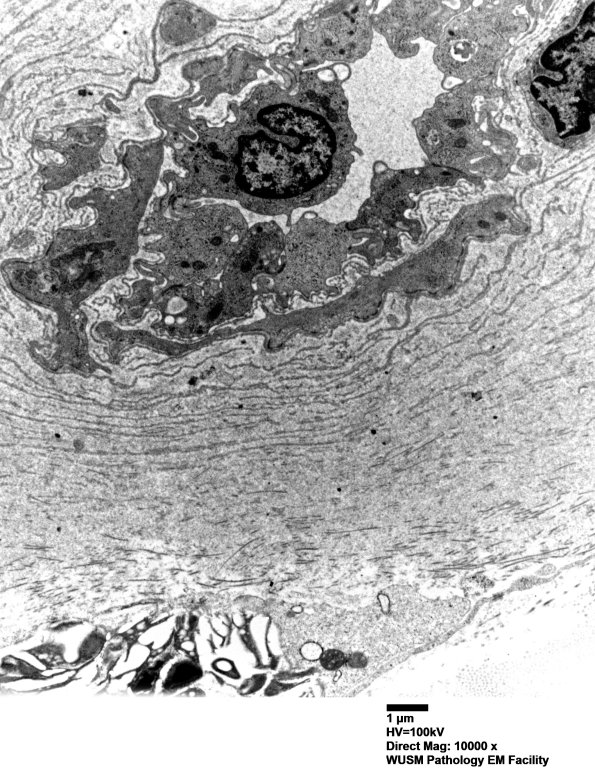

Thickening of this vessel wall consists of accumulated basal lamina fragments (arrowheads, 6C3) and collagen. (electron micrographs)